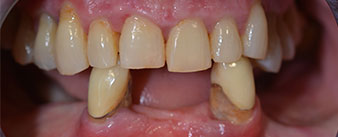

Пациентката е 64-годишна жена с частично обеззъбяване на зъби 38, 33 и 43 и частична долночелюстна протеза (Фиг. 1 и 2).